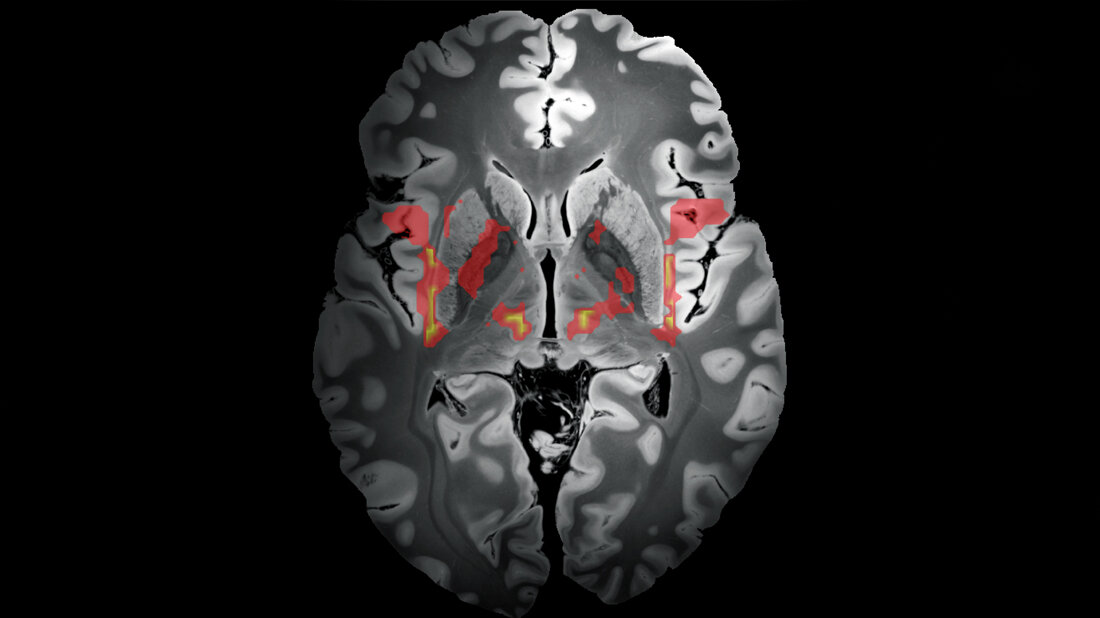

Die Forschungsgruppe konnte so zeigen, dass die Hirnschädigungen der Patientinnen und Patienten – trotz unterschiedlicher Lokalisation im Gehirn – nahezu alle Teil eines gemeinsamen Nervengeflechts waren. Dieses Netzwerk umfasste verschiedenste Bereiche des Gehirns, nämlich die Inselrinde (Cortex insularis), die Gürtelwindung (Gyrus cinguli), das Striatum, den Globus pallidus internus, den Thalamus sowie das Kleinhirn. Bassam Al-Fatly, einer der beiden Erstautoren der Studie von der Klinik für Neurologie und Experimentelle Neurologie, erläutert: „Diese Strukturen sind praktisch über das gesamte Gehirn verteilt und haben unterschiedlichste Funktionen, von der Steuerung der Motorik bis zur Verarbeitung von Emotionen. Sie alle wurden in der Vergangenheit bereits als mögliche Auslöser für Tics diskutiert, ein eindeutiger Beweis ist jedoch bisher nicht gelungen und auch ein direkter Zusammenhang zwischen diesen Strukturen war nicht bekannt. Jetzt wissen wir, dass diese Hirnbereiche ein Netzwerk bilden und tatsächlich die Ursache für Tic-Störungen sein können.“

Dass das jetzt identifizierte Nerven-Netzwerk auch für die Behandlung „klassischer“ Tics relevant ist, zeigte das Forschungsteam anhand einer Analyse von 30 Patientinnen und Patienten mit Tourette-Syndrom, denen an drei verschiedenen europäischen Behandlungszentren Hirnschrittmacher mit unterschiedlich platzierten Elektroden implantiert worden waren. Eine solche tiefe Hirnstimulation kommt aktuell in besonders schweren Fällen zum Einsatz, wenn verhaltenstherapeutische und medikamentöse Ansätze nicht ausreichend wirken. Die Berliner Wissenschaftlerinnen und Wissenschaftler bestimmten anhand von Hirnscans für jeden der 30 Tourette-Betroffenen, wo exakt die Elektroden des Hirnschrittmachers positioniert worden waren und ob diese das Tic-auslösende neuronale Netzwerk stimuliert hatten. Tatsächlich zeigte sich, dass die Symptome der Betroffenen am stärksten zurückgingen, je präziser die Elektroden das Tic-Netzwerk stimulierten.